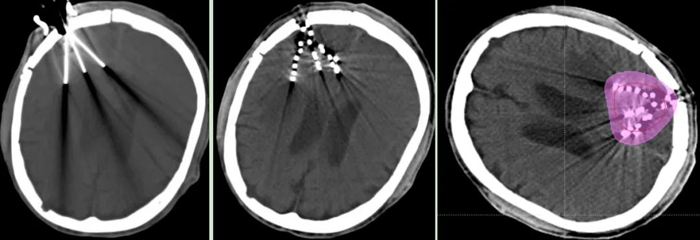

近日,我院腫瘤一科成功為一名腦膠質(zhì)母細(xì)胞瘤術(shù)后放療后復(fù)發(fā)患者,實(shí)施“CT引導(dǎo)腦部腫瘤125I放射性粒子植入術(shù)”。

經(jīng)腫瘤科、神經(jīng)外科、影像科等科室多學(xué)科討論,認(rèn)為患者無再次手術(shù)及放療指征,決定行“CT引導(dǎo)125I放射性粒子植入術(shù)”。經(jīng)周密術(shù)前準(zhǔn)備,在神經(jīng)外科吳超副主任醫(yī)師協(xié)作下,張開賢主任帶領(lǐng)粒子治療團(tuán)隊(duì)歷經(jīng)2個(gè)小時(shí),在CT精準(zhǔn)引導(dǎo)下,成功完成了125I放射性粒子植入術(shù),現(xiàn)恢復(fù)良好。術(shù)后劑量驗(yàn)證,達(dá)到術(shù)前計(jì)劃要求。

125I放射性粒子植入術(shù)屬于近距離放療的范疇,是在影像學(xué)引導(dǎo)下,精準(zhǔn)地將125I粒子植入在腫瘤病灶內(nèi),通過125I持續(xù)釋放低能量的γ射線,達(dá)到殺傷腫瘤細(xì)胞,控制腫瘤生長的目的。由于125I粒子釋放的γ射線能量小,射程短,劑量跌落快,因此,腫瘤病灶內(nèi)照射劑量很高(可達(dá)到外照射的2-3倍),而周圍正常組織劑量低,從而達(dá)到最大程度殺傷腫瘤細(xì)胞,而周圍正常組織不受損傷或輕微損傷的目的。目前已廣泛應(yīng)用于各部位腫瘤的治療,為惡性腫瘤的治療增加了一種新手段。